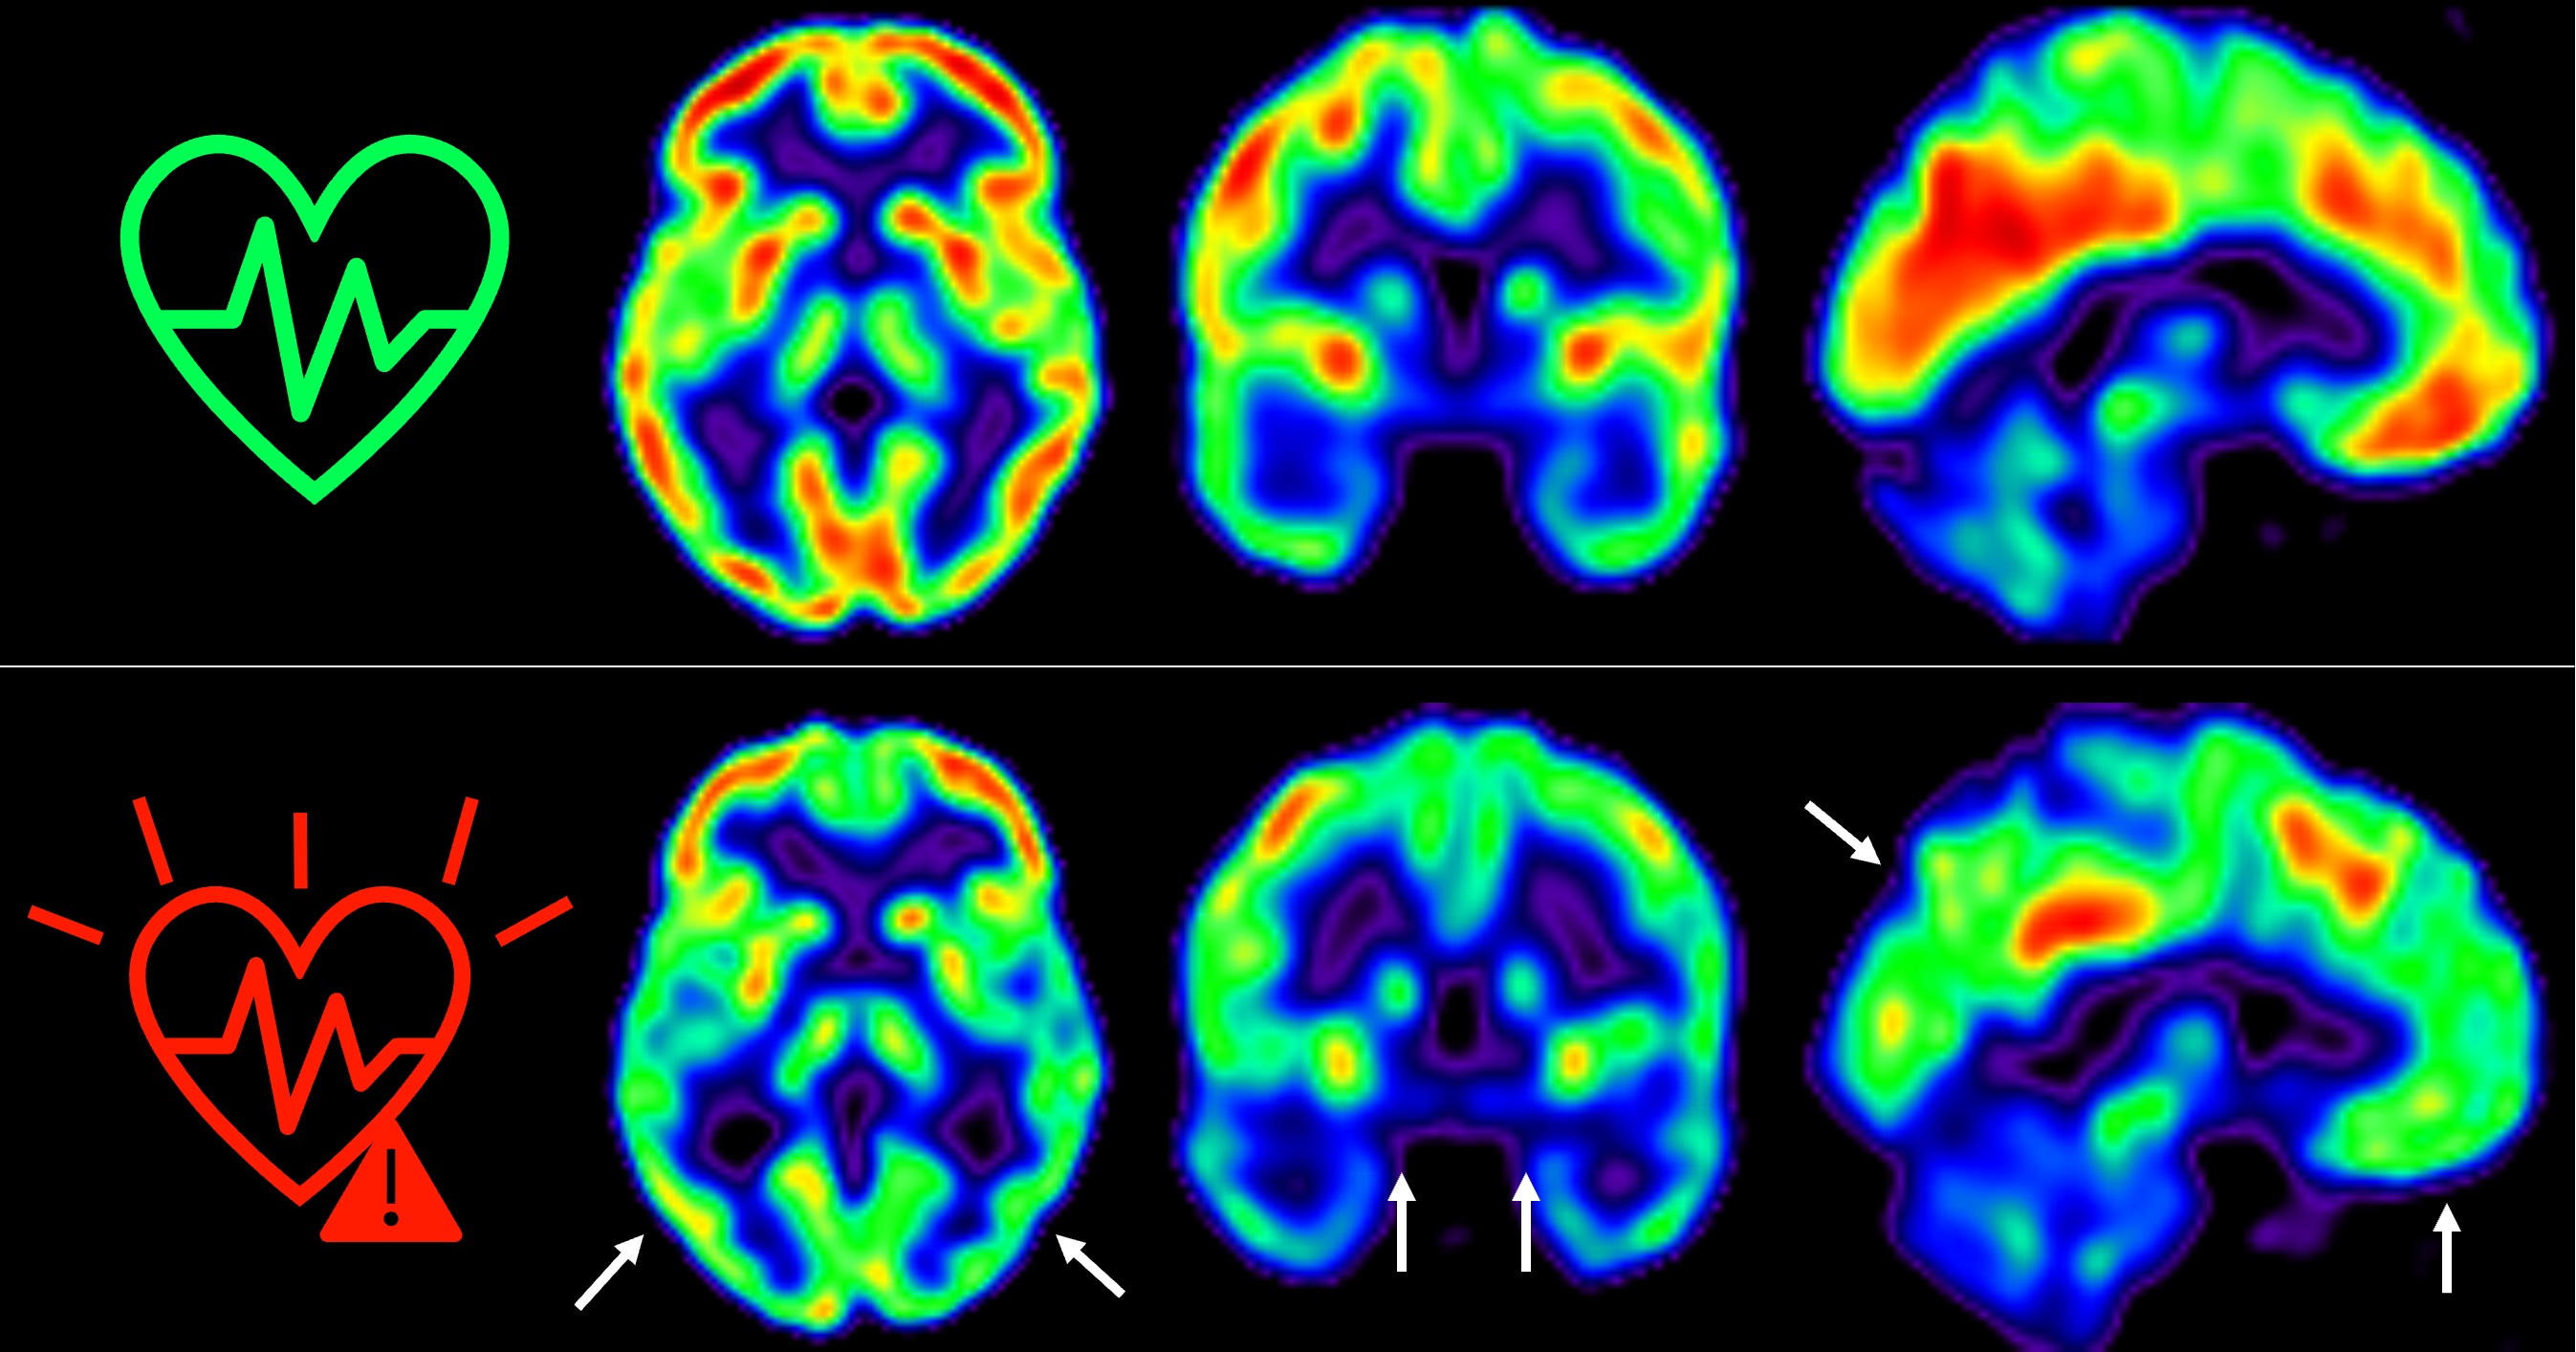

Influencia de marcadores genéticos evolutivos relacionados con el neurodesarrollo fetal en la esquizofrenia